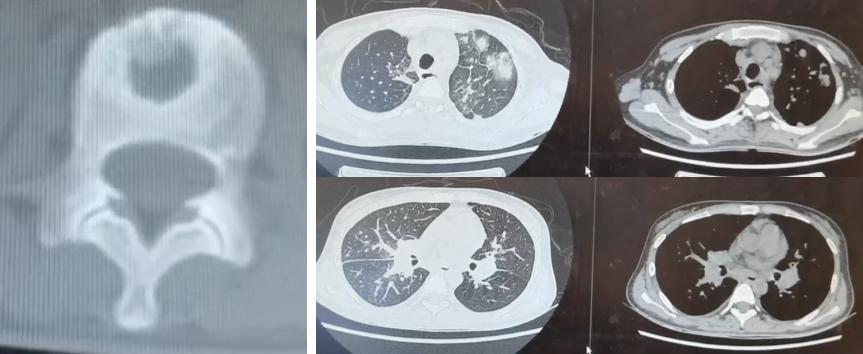

影像可见患者右下肺有较大的实变:

胸水是血性的,我们下了决心去穿刺,肺穿刺组织培养48小时发现根毛霉,病理也看到了丝状真菌: